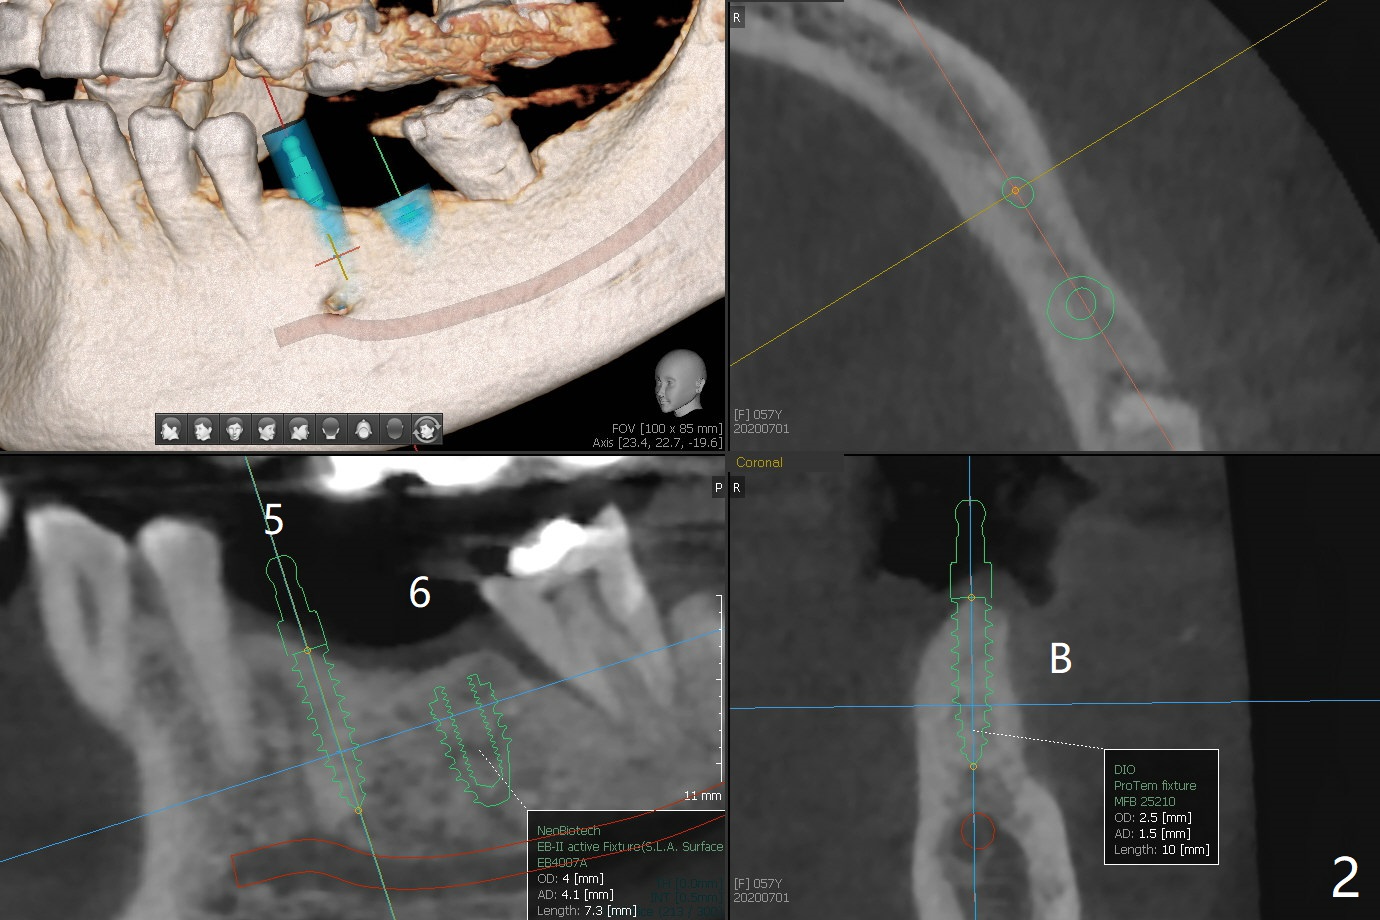

57岁女缺失四个下牙(图一),由于保险限制,先考虑左边种植(图二,三),主要问题是牙槽嵴狭窄(不过左上牙桥做的太长了,尤其是5,6(图一'),造成下面垂直距离缩短,修复困难。总之,她的牙齿显得短小)。牙槽嵴狭窄处理方法:切口,使用导板用bone trimmer和最细钻头(point drill或者2.2毫米)钻洞(图四:黑圆圈),到深度,然后用圆形骨锯在牙槽嵴顶部劈开(弯曲红线),必要时做三个垂直骨切口(图六),徒手利用旋转式骨扩张器,或者骨凿,推开颊侧骨板。也准备外科钻头(新的)。放置导板和钻头除去舌侧骨板,最后在5,6分别植入3.0 或者3.5毫米,4.0或者4.5毫米植体。如果初步稳定性好,即刻修复,主要防止7继续近中倾斜,必要时,7近中(图一*)植骨。抽血制备两个PRF膜和粘性骨块。